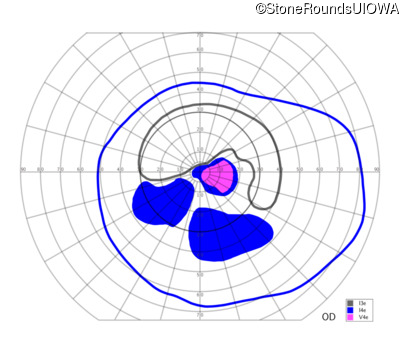

AR Stargardt Disease (IIA)

AR Stargardt Disease (IIA)

| Age at visit: 12 years |

| Age at visit: 13 years |

| Age at visit: 15 years |